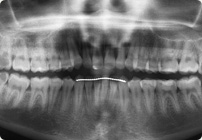

Caso: 12 años

Adolescente: Clase II

Dental Maxilar Protrusion

Extract U4’s/L5’s

4 series de alambres:

.016″, 022″, .0215″ x .028″, .019″ x .025″ Trenzado

Elástico clase 2 2oz. TP amarillos y verdes

Retenedores: Interior Fijo de TMA y Hawley en superior

Tiempo de tratamiento: 15 Visitas